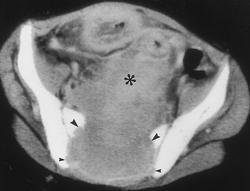

Гигантоклеточная опухоль.

Злокачественная гигантоклеточная  опухоль возникает из доброкачественной (частота 10-20%). После операции возможно появление рецидива опухоли.